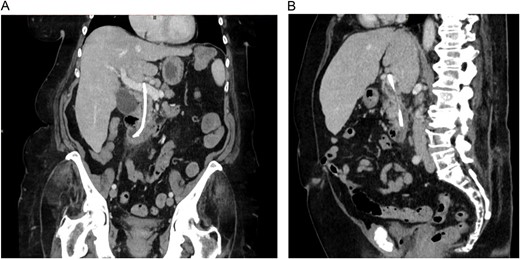

One month later, the patient once again presented to the local emergency department with fever (39.5°C) and pain in the upper right quadrant. Blood tests showed sign of cholangitis with CRP of 144 mg/L and total bilirubin of 43 mg/L. An abdominal CT was performed and stent migration into the portal vein was suspected (Fig. 1).

CT images showing the migrated common bile duct stent in the portal vein. (A) Coronal view. (B) Sagittal view.